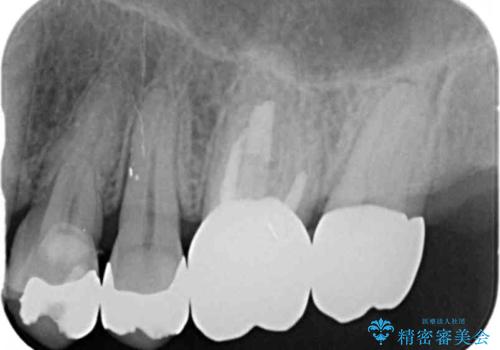

- 失ってしまった左下の奥歯にインプラント治療を受けたいと来院されました。

左下の欠損部には強度・表面性状に優れるストローマン社製インプラントを埋入し、合わせて噛み合う上顎の歯もクラウン再補綴による整備を行い安定した咬合関係の構築を目指します。

歯を失った期間が長くなると、対合する歯が伸びてくることによる補綴スペースの狭小化がしばしば見られます。

今回左下にインプラント治療を行うにあたり、対合する上顎の歯もいっしょに治療を行ったことで安定した咬合関係を構築することができました。